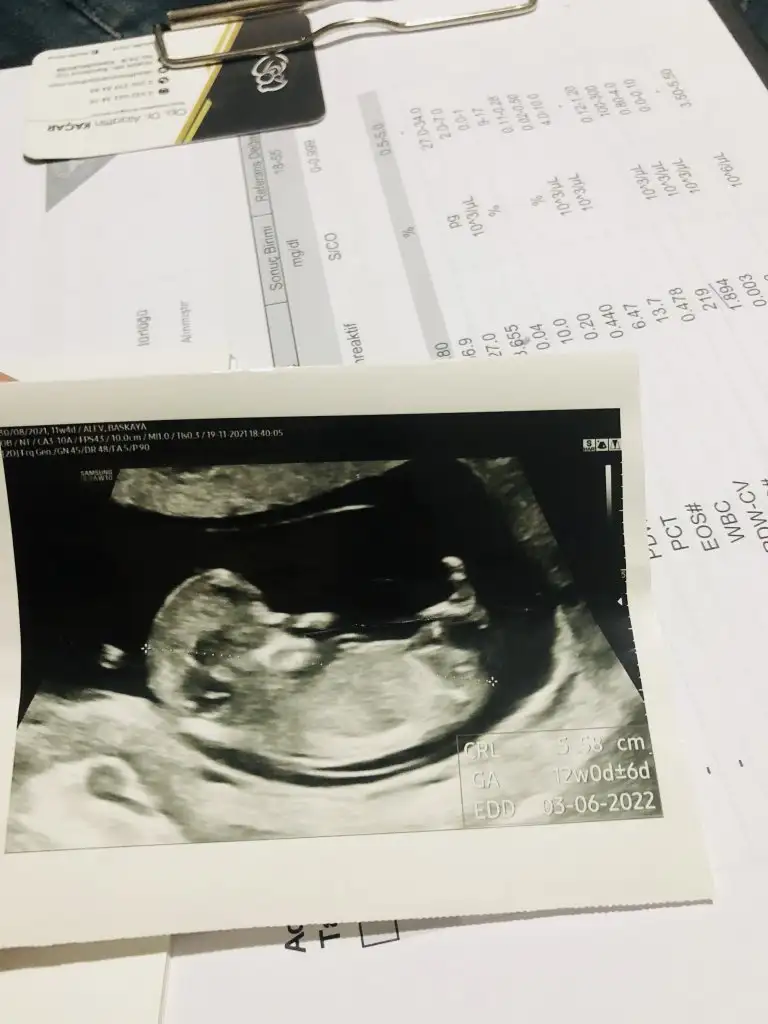

Belli belirsiz tam o bölge ama sanki kız gibi canım. Eki Görüntüle 2957287

Bana doktor zaten kız dedi.